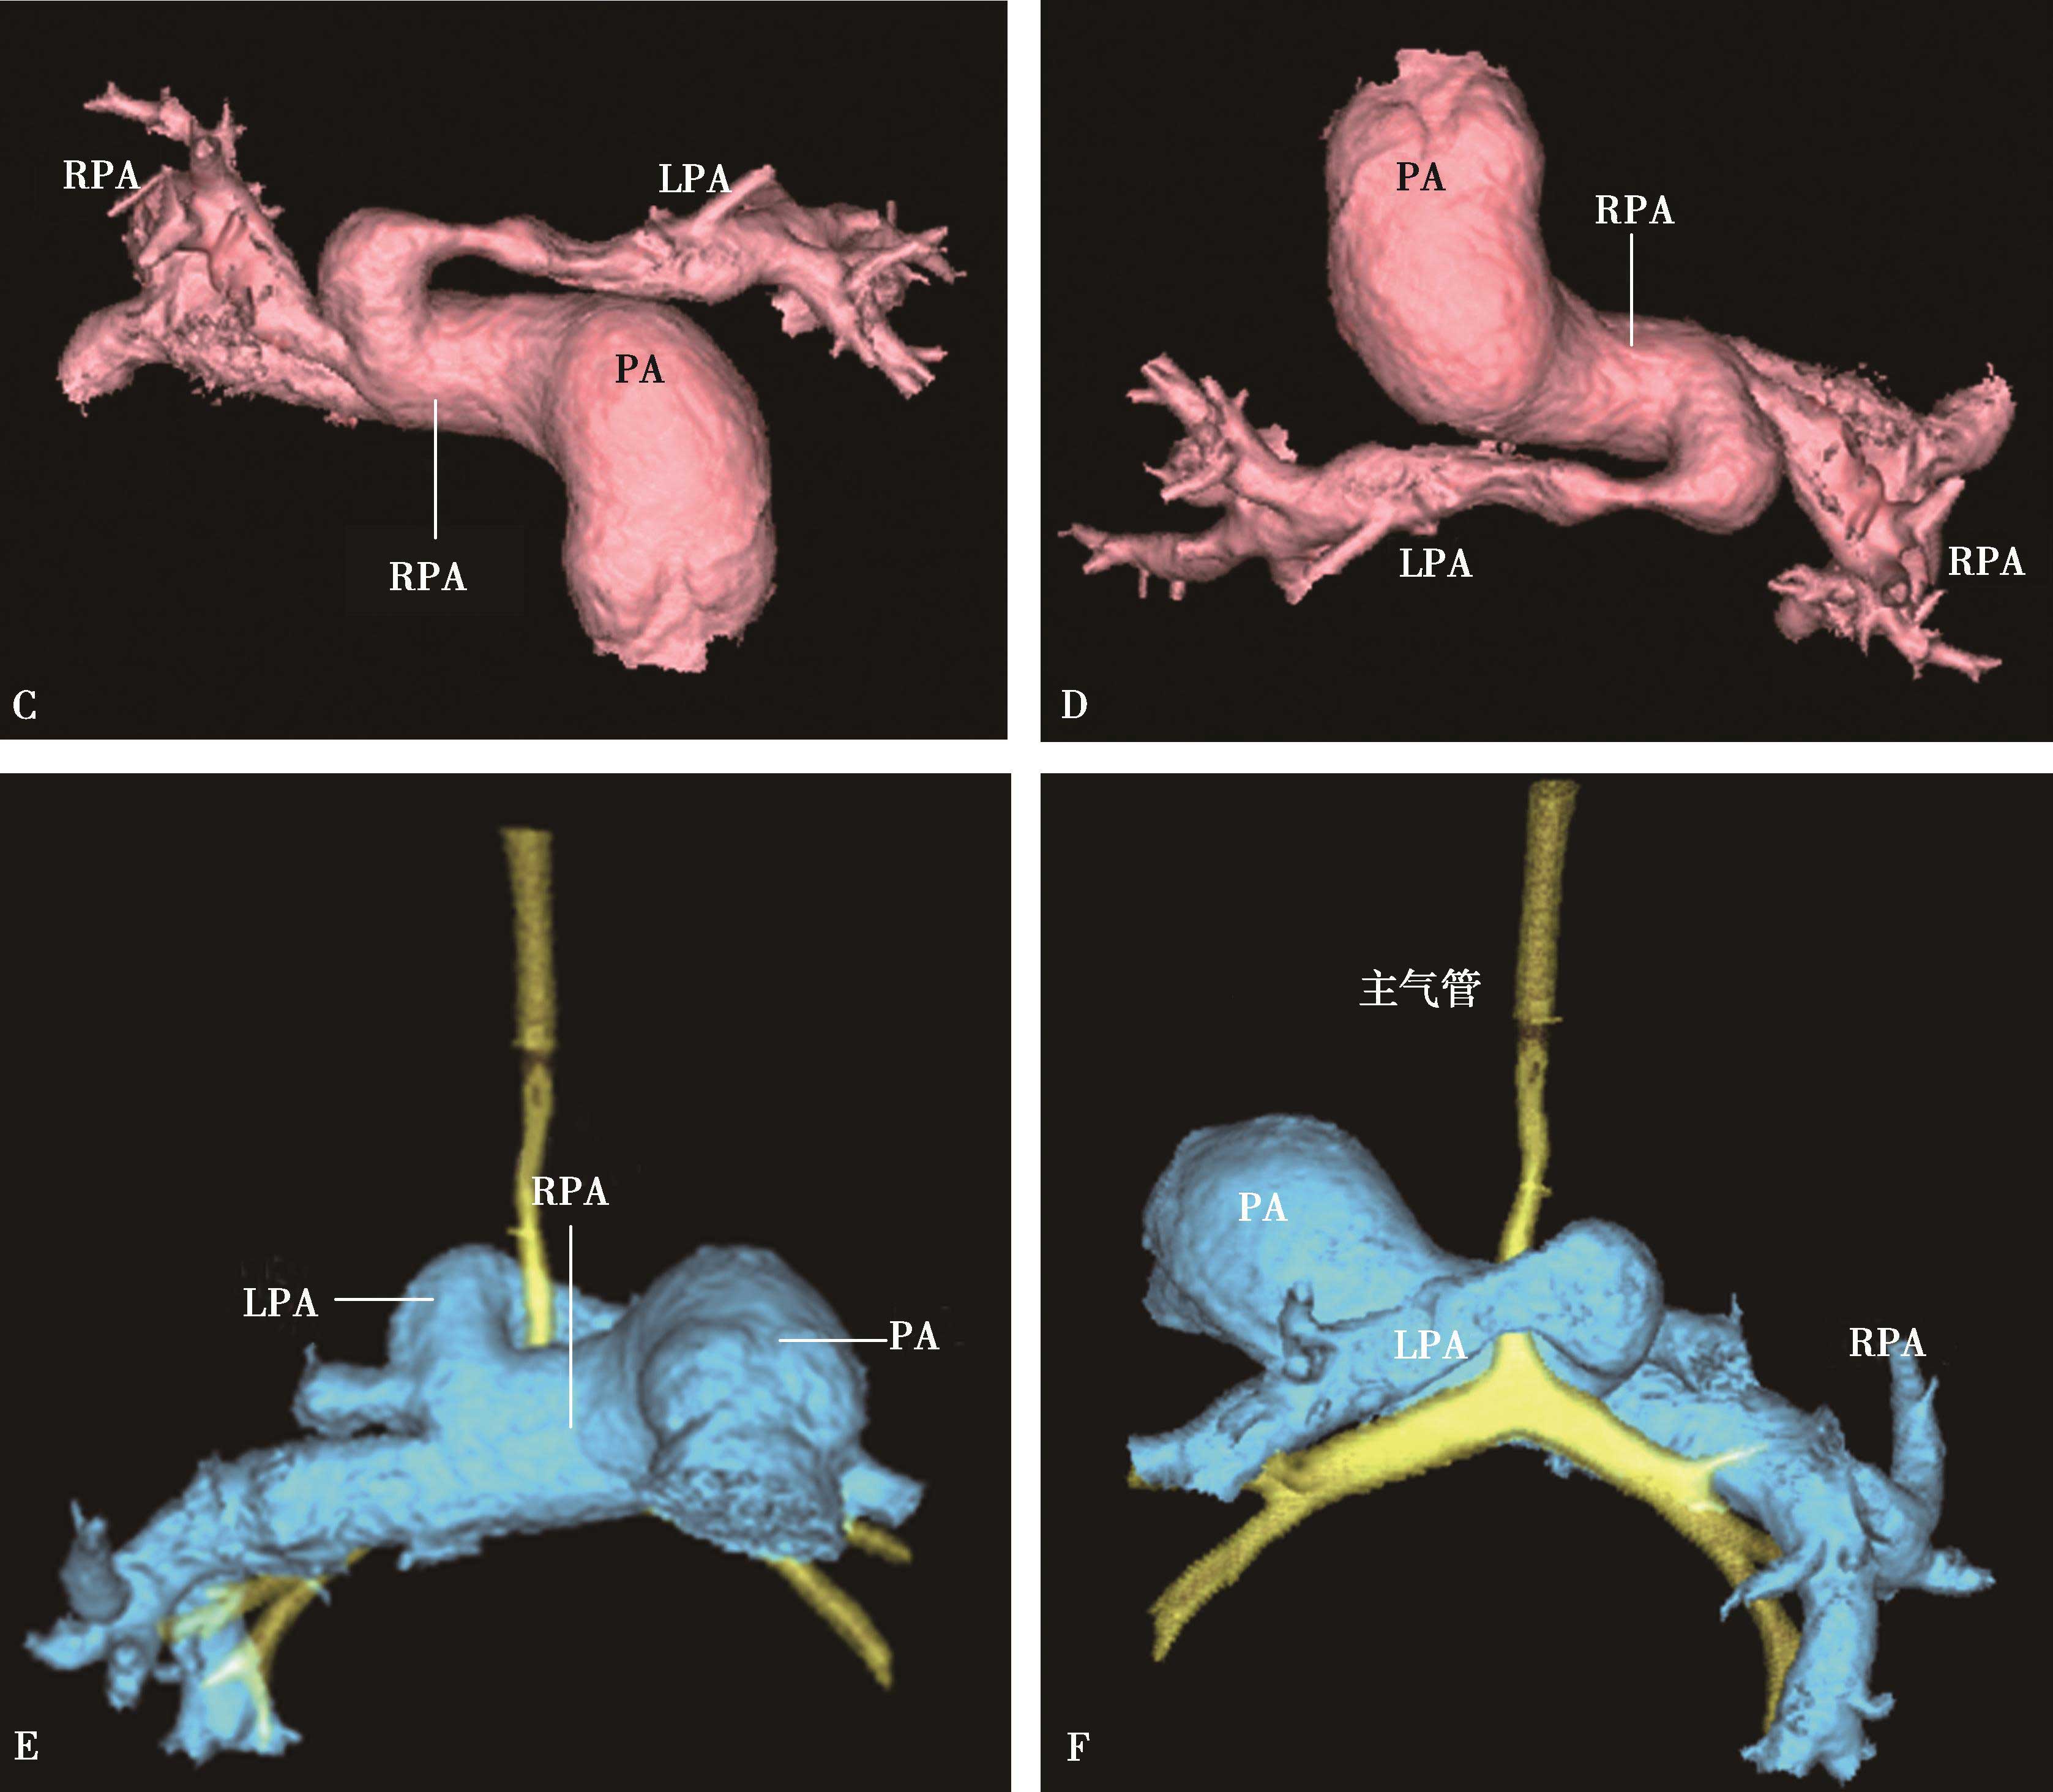

1)主肺动脉干或/和左右肺动脉干梭形瘤样扩张,腔内不同程度附壁血栓(图8-5-4)。

图8-5-4 反复发作口腔溃疡,临床诊断白塞病

横断图像。A~C.主肺动脉、瘤样扩张,左右肺动脉瘤样扩张,不规则附壁血栓(↑);D~F.三维重建主肺动脉及左右肺动脉瘤样扩张,红色为附壁血栓(↑),波及肺叶分支;CT诊断:肺动脉瘤累及主肺动脉、左右肺动脉及叶分支,附壁血栓形成,病变性质考虑为白塞病

2)肺动脉叶段分支瘤样扩张,真性或假性动脉瘤形成,腔内不同程度附壁血栓(图8-5-5)。